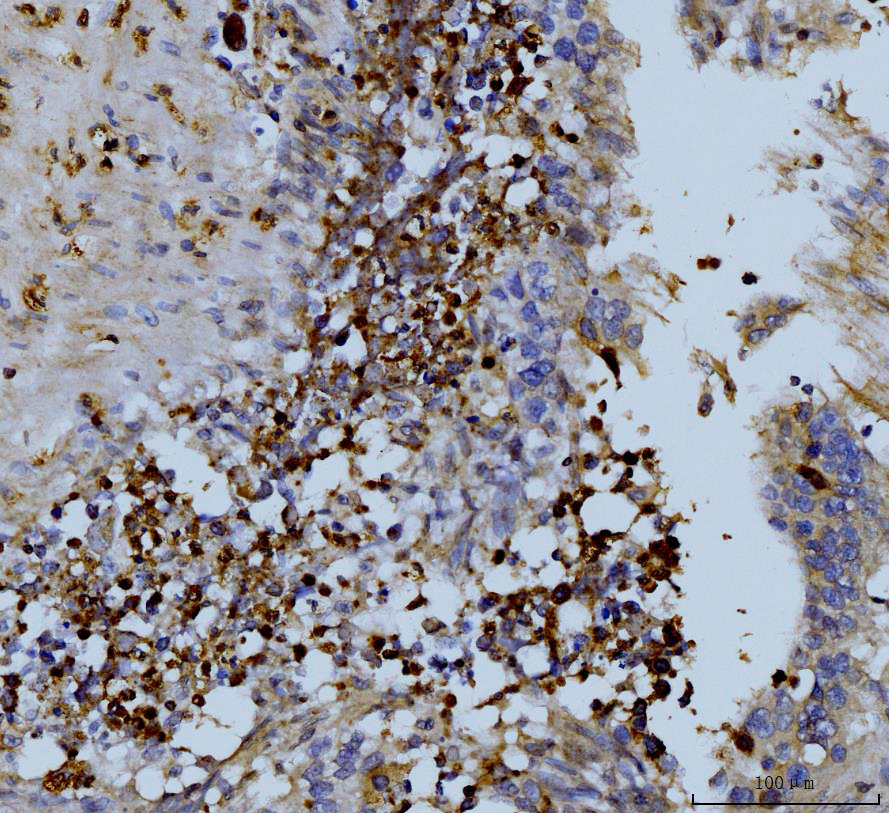

IHC analysis of MMP9 using anti-MMP9 antibody (PB0709).

MMP9 was detected in a paraffin-embedded section of human Lymph nodes of gastric adenocarcinoma tissue. Biotinylated goat anti-rabbit IgG was used as secondary antibody. The tissue section was incubated with rabbit anti-MMP9 Antibody (PB0709) at a dilution of 1:200 and developed using Strepavidin-Biotin-Complex (SABC) (Catalog # SA1022) with DAB (Catalog # AR1027) as the chromogen.